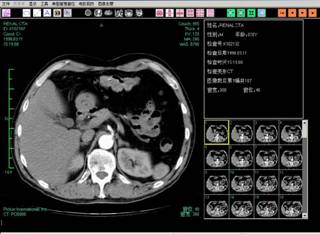

[计算机视觉与图像处理]

medimg.jpg

实验室近年来在计算机视觉、图像处理与智能分析方面开展深入研究,聚焦于人工标注“小、弱、少”场景下的图像自动检测、分类等核心计算机视觉任务,设计了多种新颖的半监督、跨领域自适应深度学习方法,相关技术在国际上处于领先水平。多篇研究成果发表在人工智能领域著名国际期刊IEEE JBHI、Artificial Intelligence in Medicine、智能医学影像分析国际顶级会议 MICCAI'2021等。